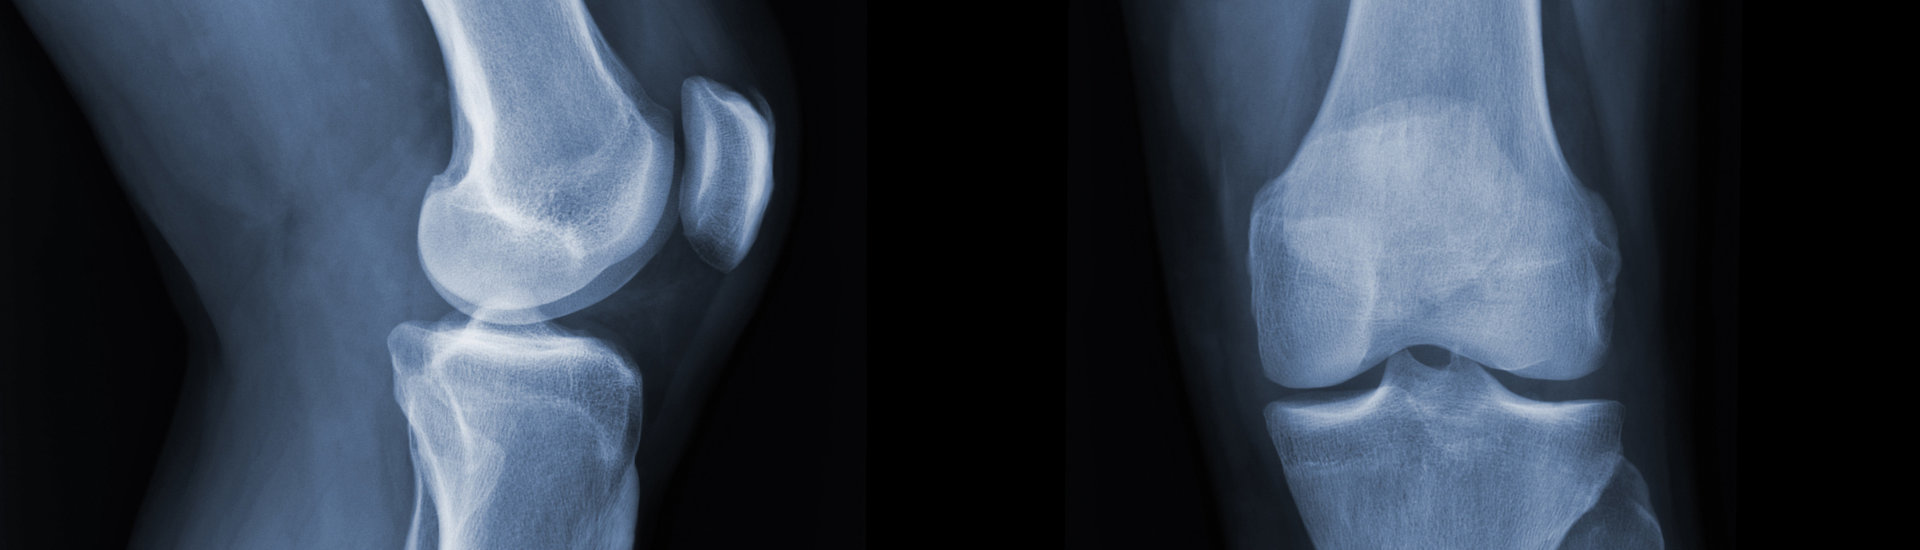

L’esame RX Assiali della Rotula, effettuato nel Poliambulatorio S-Medical Group di Sora, si basa sull’uso dei raggi X per acquisire immagini interne del corpo. Durante la procedura, il paziente è posizionato in modo ottimale e sottoposto a una breve esposizione ai raggi X. Le immagini risultanti vengono poi analizzate dagli specialisti per individuare eventuali anomalie.

Durante l’esame RX Assiali della Rotula, il trasferimento energetico è realizzato tramite l’emissione di raggi X a bassa dose che attraversano il corpo del paziente. Questi raggi interagiscono con i tessuti corporei, generando un’immagine catturata su una pellicola o su un rivelatore digitale. L’immagine finale viene quindi esaminata dagli specialisti per fornire una diagnosi accurata.

L’esame RX Assiali della Rotula nel Poliambulatorio S-Medical Group di Sora è eseguito con grande attenzione e professionalità. Durante l’esame, il paziente viene sistemato in posizione adeguata, generalmente eretta o seduta. Un’apparecchiatura radiografica è utilizzata per inviare una breve esposizione ai raggi X alla zona della rotula, e tutto il processo è guidato da professionisti altamente qualificati.